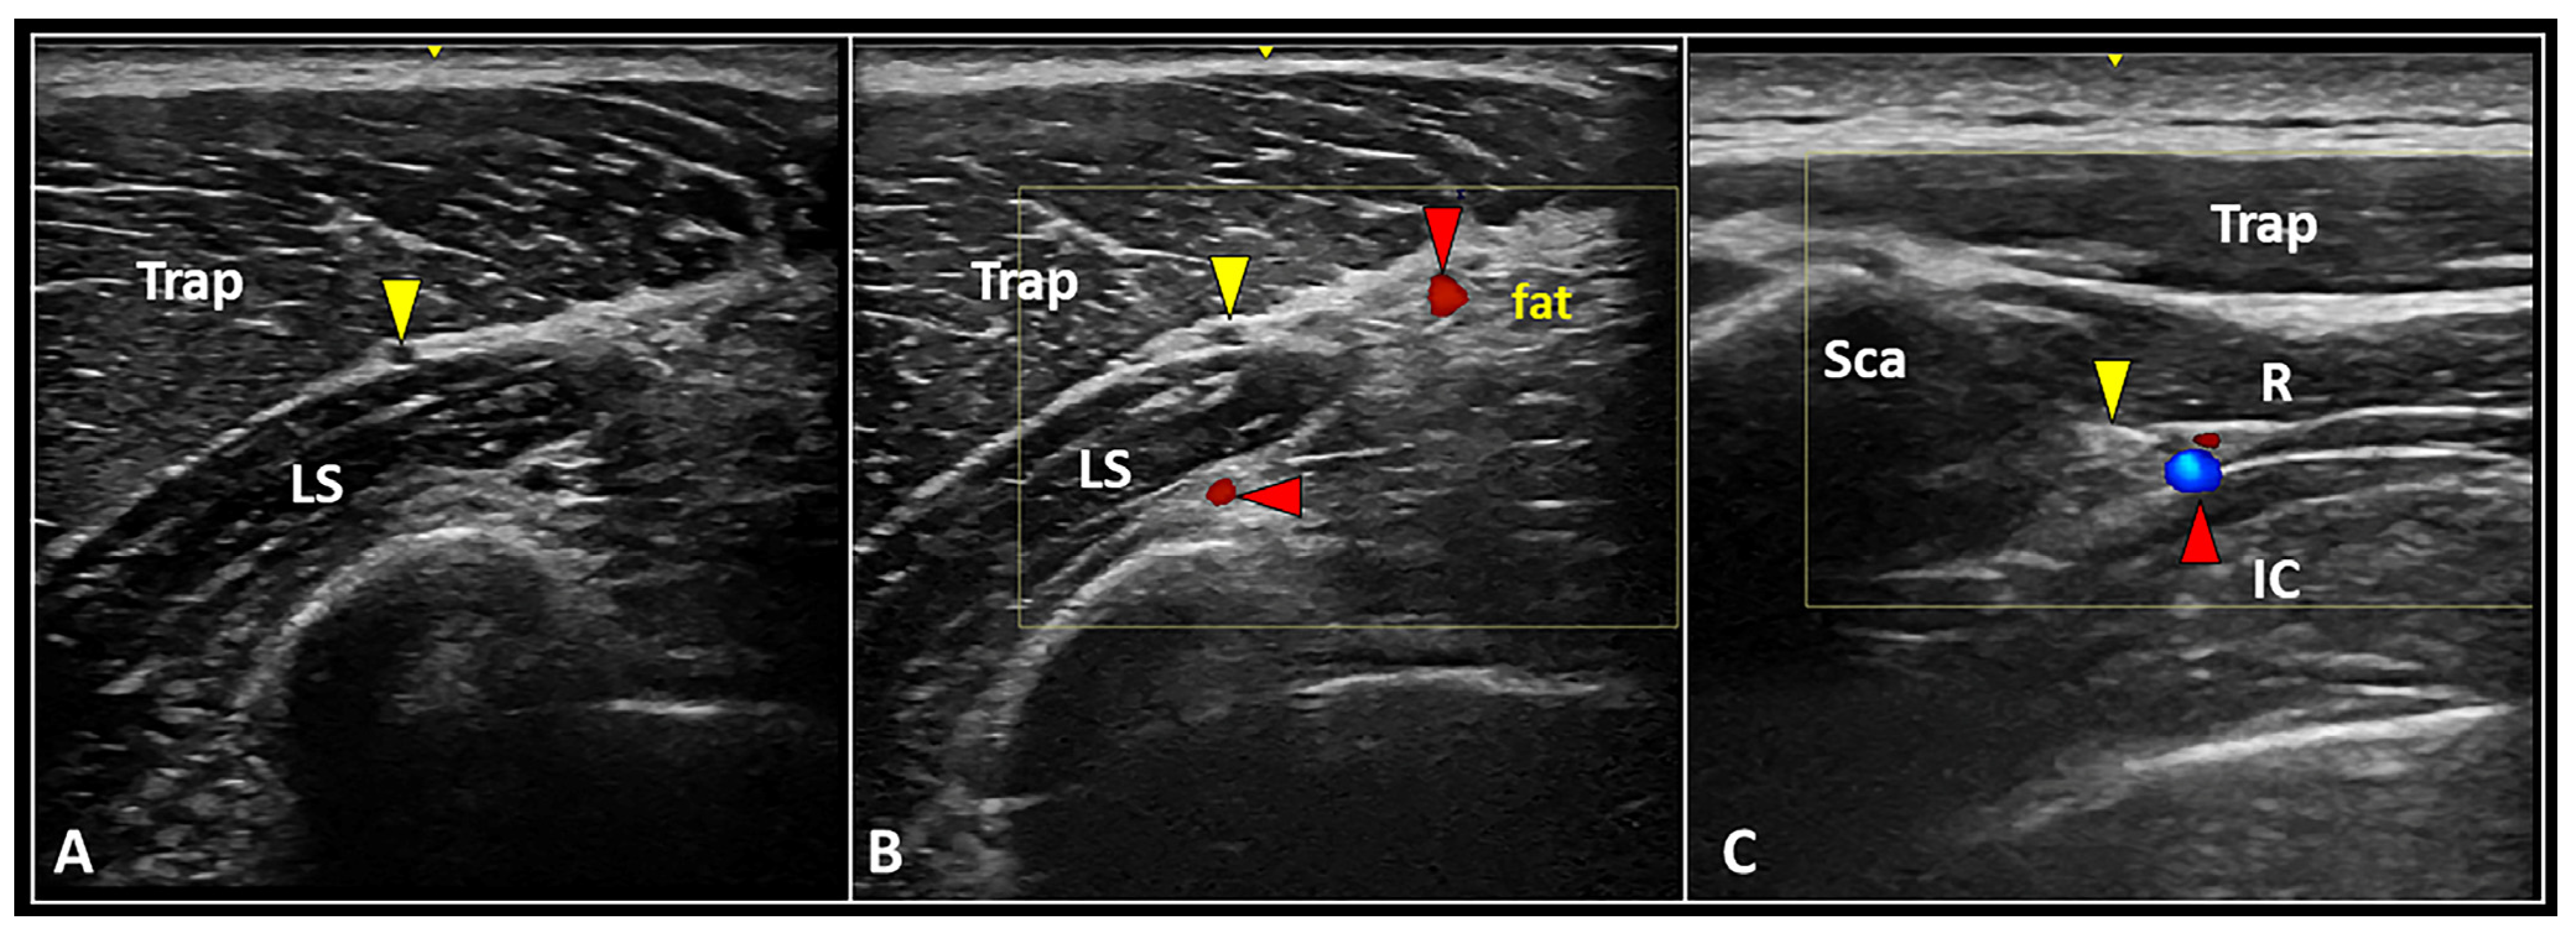

Second, B-mode evaluation should be coupled with power Doppler imaging for each and every patient in clinical practice. Not simply the intra/peri-nodular perfusion pattern, but also the eventual location of large neurovascular elements surrounding the MTrP, can be promptly assessed (Figure 2) [11]. The latter is paramount to avoid unintentional collateral injury—in other words, to plan for an accurate and safe procedure.

Figure 2.

Longitudinal US scan (A) clearly shows the anatomical location of the spinal accessory nerve (yellow arrowhead) within the interfascial space between the trapezius (Trap) and levator scapulae (LS) muscles. Accurately setting the color Doppler box, superficial and deep branches of the transverse cervical artery (red arrowheads) can be promptly identified to plan a safe intervention (B). Transverse ultrasound scan with color Doppler imaging (C) shows the dorsal scapular nerve (yellow arrowhead) and artery (red arrowhead) running inside the interfascial plane between the rhomboid (R) and intercostalis (IC) muscles medial to the medial edge of the scapula (Sca).

Peripheral nerves. The peripheral nerves most commonly involved in cervical MPS are the spinal accessory nerve (SAN) and the dorsal scapular nerve (DSN). Diffuse muscle spasm and/or bad posture can lead to chronic entrapment of these nerves, with progressive development of cervical neuropathic pain. Accordingly, several authors have proposed a US-guided block of the SAN [26] and/or DSN [27] to manage cervical myofascial pain refractory to first-line conservative treatments [23].

The SAN can be easily identified within the interfascial plane between the upper fibers of the trapezius and levator scapulae muscles (Figure 2). Before performing the US-guided block, the authors strongly recommend assessing the anatomical area with power Doppler imaging to promptly identify the superficial branch of the transverse cervical artery running within the same interfascial plane [28].

After piercing the medial scalene muscle, the DSN can be sonographically detected beneath the levator scapulae and rhomboid muscles, accompanied by the dorsal scapular artery (Figure 2) [29]. Of note, interscapular pain is quite often a referred pain originating from the neuro-myofascial tissues of the cervical spine. Herewith, the authors strongly suggest sonographically assessing the thoracic paraspinal and peri-scapular muscles to check for the eventual presence of muscle edema and/or injury at this level [30].

In patients with diffuse cervical muscle contraction and absence of clinically and/or sonographically detectable painful MTrPs, US-guided injections of the interfascial planes can be performed to selectively block specific peripheral nerves. Indeed, within the virtual space between different muscular layers of the cervical spine, many neural structures run, and they are surrounded by connective tissue rich in collagen fibers and loose connective tissue of the areolar type with a variable number of adipose cells [23]. Among many, the SAN and the DSN are the most commonly involved nerves in cervical MPS [26,27].

The SAN can be easily visualized and blocked within the anatomical interface between the trapezius and levator scapulae muscles (Figure 2) [28]. The sonographic pattern similar to a “black ball” is related to the mono-fascicular architecture of the SAN at this level [43]. Positioning the US probe in the longitudinal axis, a cranial-to-caudal (or vice versa) approach can be performed to inject the intermuscular plane with the anesthetic agent, blocking the target nerve. In chronic peripheral nerve entrapments with fibrosis of the subsynovial connective tissue, perineural hydro-dissection using high volume improves kinematic properties of the entrapped nerve and its axoplasmic flow [44]. Accordingly, the authors suggest using high volumes rather than a few milliliters to “open” the interfascial plane. Lastly, taking into account the surrounding vascular structures, e.g., superficial and deep branches of the transverse cervical artery, power Doppler assessment in the pre-procedural phase should always be performed for a safer needle pathway (Figure 2).

The DSN can be promptly visualized and blocked within the anatomical plane between the rhomboid muscles and the thoracic wall (Figure 2) [25]. An in-plane technique with a medial-to-lateral approach is commonly preferred, since the DSN and the corresponding artery are in close proximity to the medial edge of the scapula. Unlike the SAN block, the DSN block is usually performed by more experienced physicians due to the presence of vital anatomical structures (e.g., lung, pleura) immediately deep into the target.